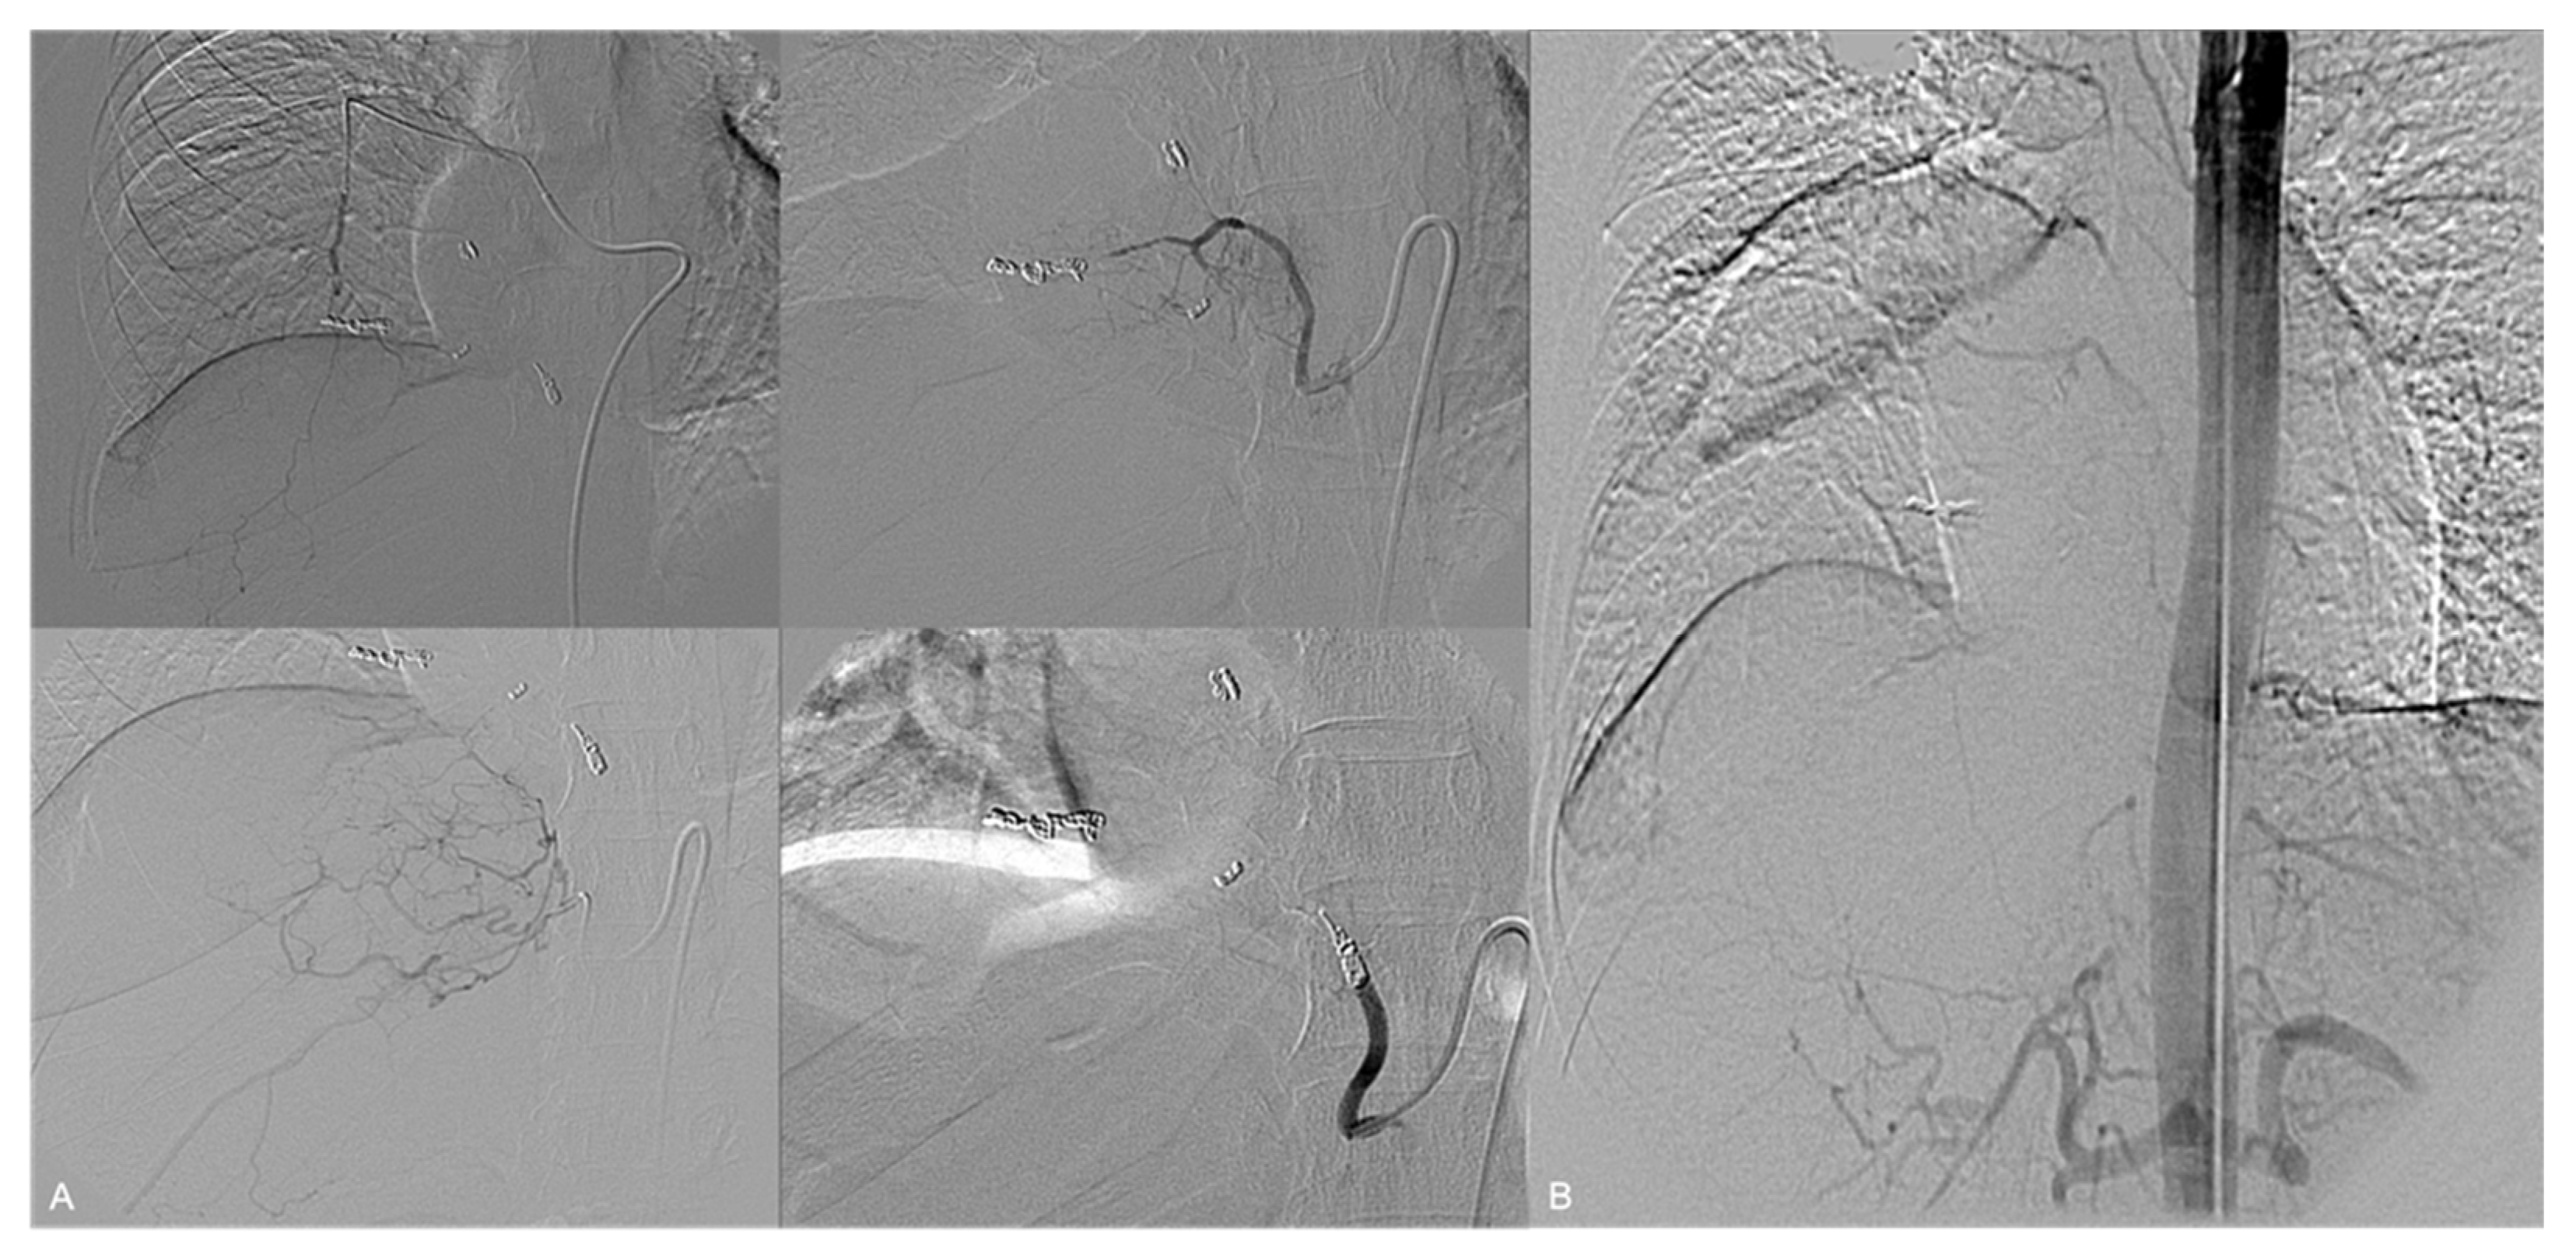

3. Results